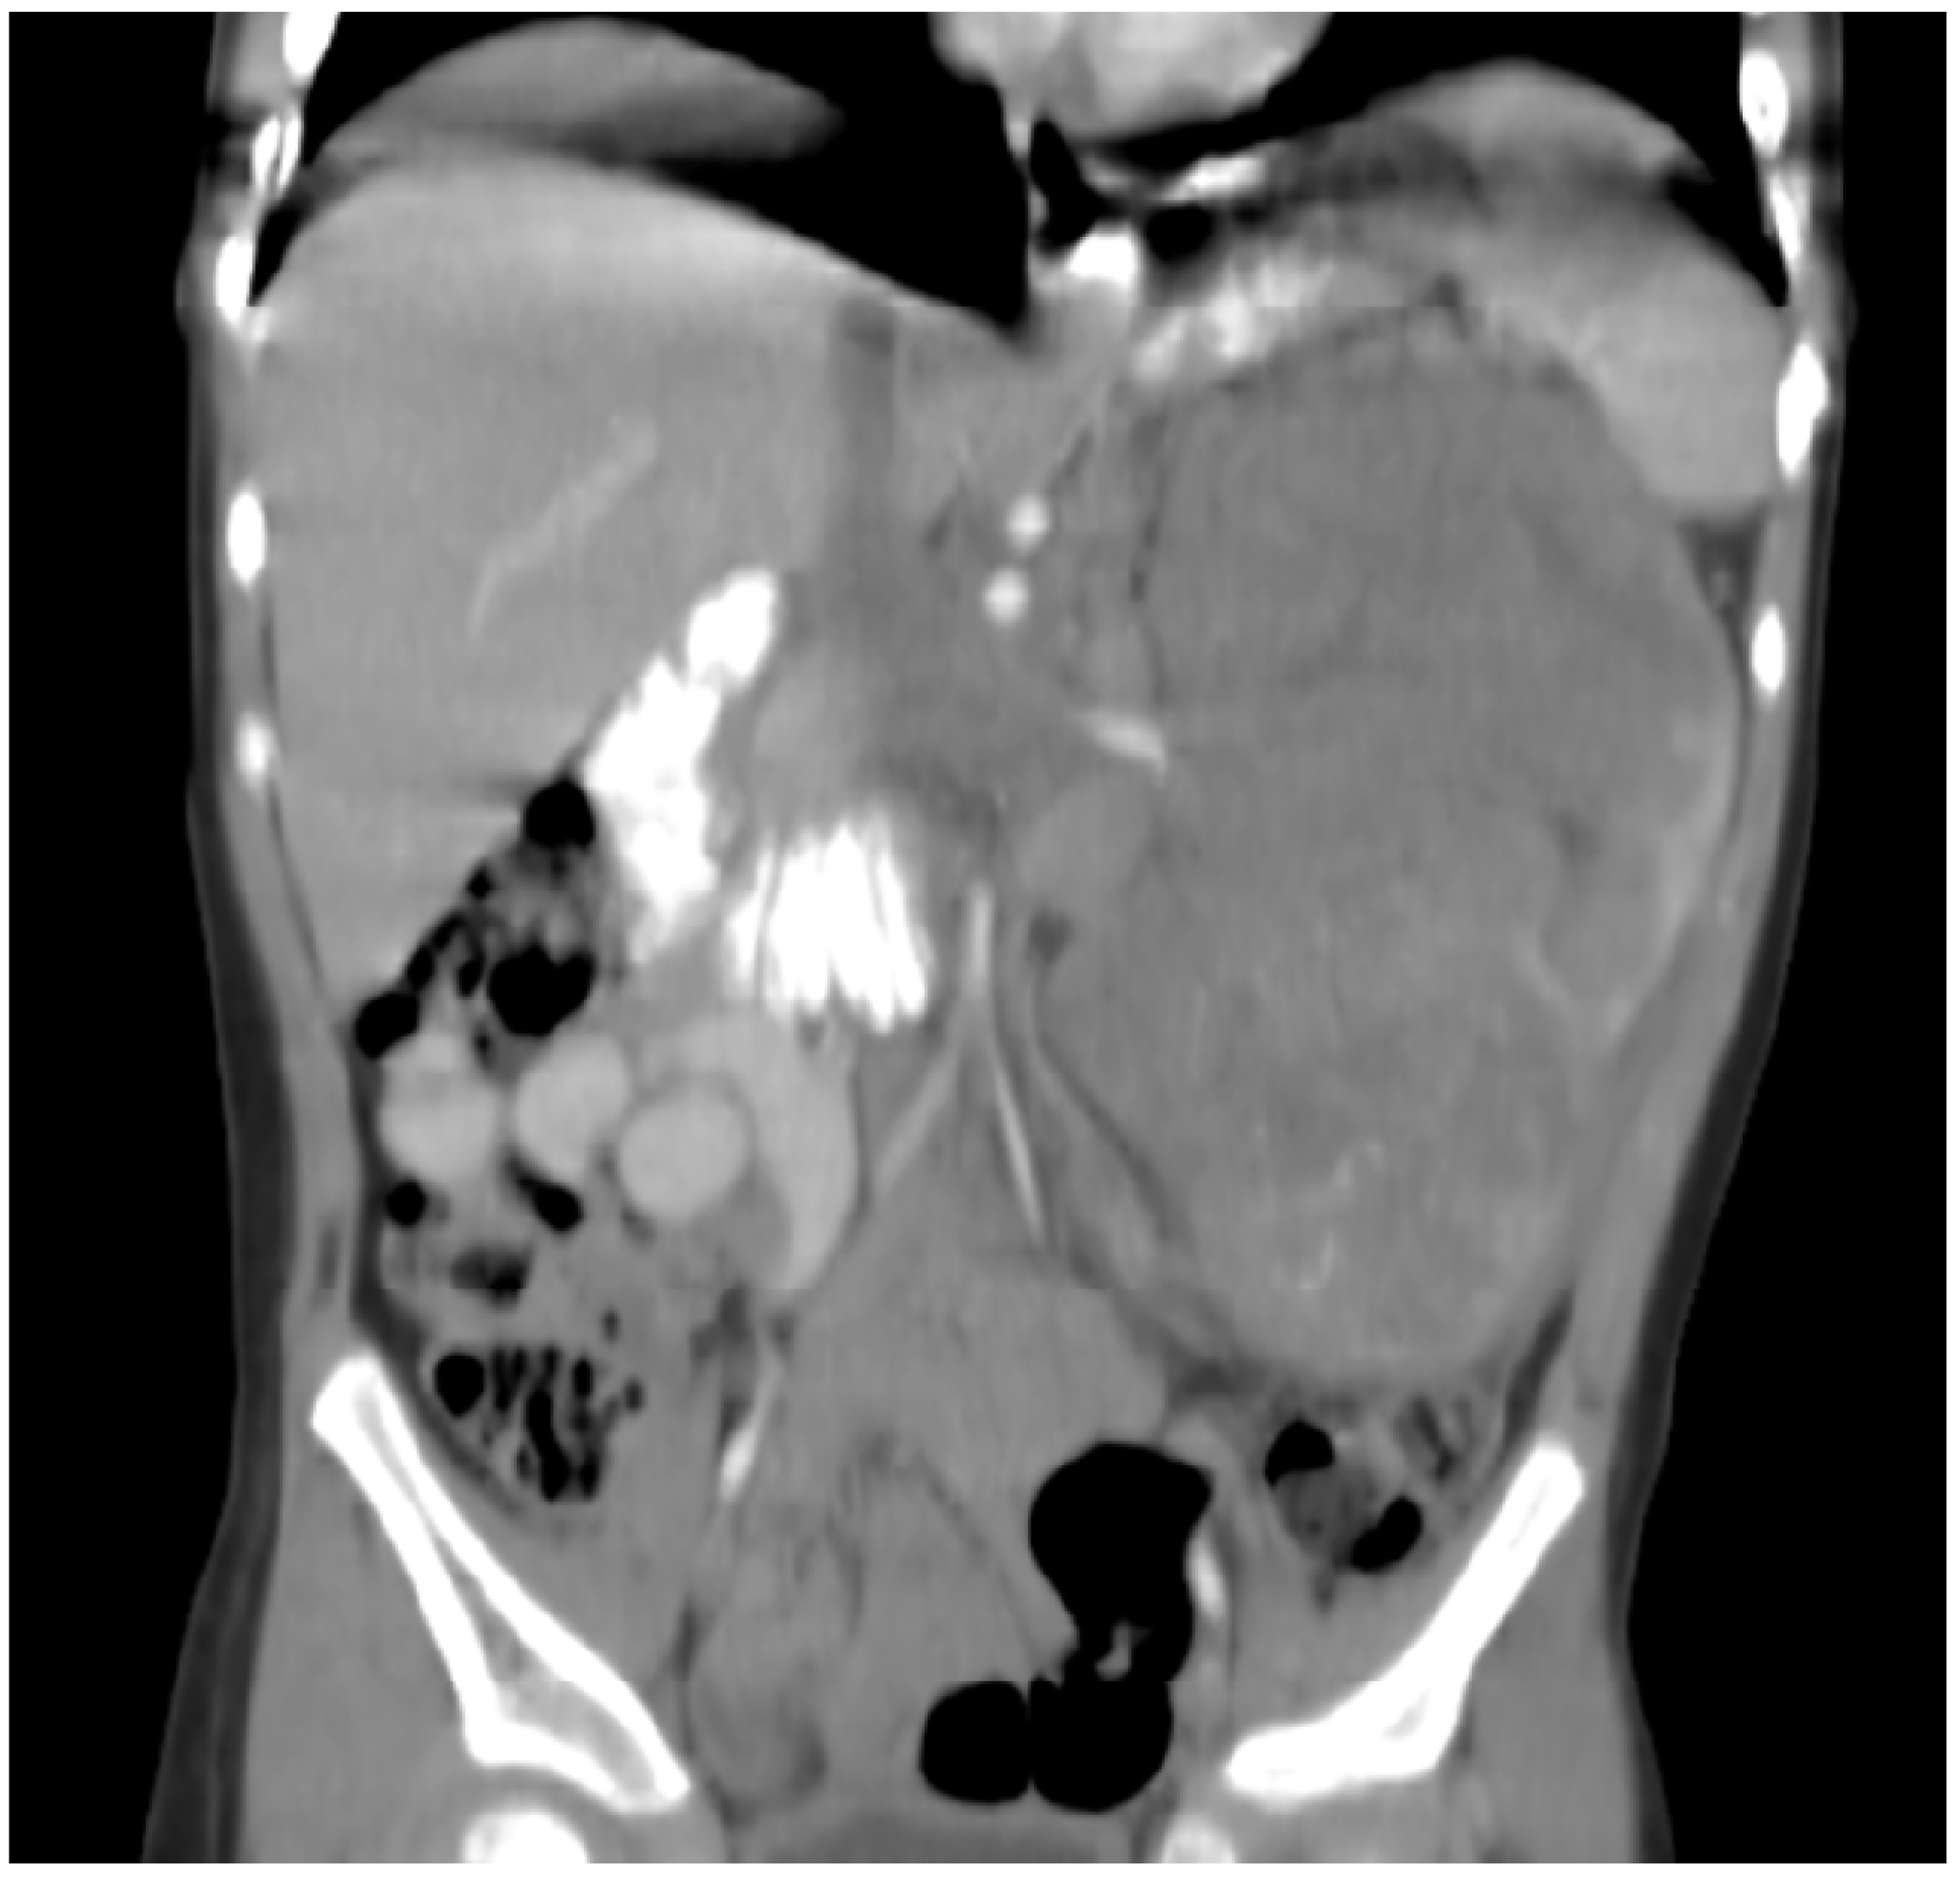

This patient is a Hispanic girl found to have a large cervicomedullary tumor with a cervico-thoracic central syrinx with tumor seeding when she presented with right shoulder drop and right upper-extremity weakness at 3 years of age (Figure 4A). She had resection of the cervicomedullary portion of the tumor. Evaluation revealed a type 2 neurocytoma of the spine.

Figure 4.

Patient 6: (A) MRI shows a 4.5 cm homogeneously enhancing expansile intramedullary tumor involving the medulla and upper cervical cord down to the level of C3–C4 (arrow) with an elongated syrinx extending inferiorly to the T3–T4 level; (B) the tumor was removed and treated with radiation but came back, for which it was treated with nine cycles of topotecan–ifosfamide–carboplatin with no significant change in tumor size (arrow) but significant toxicity, for which treatment was changed to metronomic chemotherapy; (C) after 3 months on metronomic chemotherapy, the patient recovered from toxicity and the tumor was slightly decreased; (D) the tumor was stable at the end of 4 years of metronomic chemotherapy.

She subsequently received intensity-modulated radiotherapy to the tumor bed and residual cervico-thoracic tumor. Following radiation, a residual 11 mm expansile cervicomedullary nodule, centered at the C3–C4 level, was documented. Five months later, she developed progressive disease with increased size of the cervicomedullary nodule to 15 mm and development of a new second focus of enhancement on the ventral aspect of the spinal cord at C2. She was treated with topotecan, ifosfamide and carboplatin (TIP). She had significant hematologic toxicity and infectious complications during this treatment and no change in tumor size after nine cycles (Figure 4B), for which she was changed to metronomic chemotherapy with 21 days of temozolomide (60 mg/m2 day) aleternating with 21 days of CTX (50 mg/m2), VA (15 mg/kg), celecoxib (250 mg/m2/day) and bevacizumab (5 mg/kg IV every 3 weeks). Tumor response was noted 3 months after treatment with decreased tumor size to 9–10 mm (Figure 4C). Tumor size remained stable on subsequent studies, and temozolomide and CTX were stopped at 18 months, celecoxib and VA were stopped at 36 months, and bevacizumab was stopped at 48 months (Figure 4D). Metronomic chemotherapy was restarted after tumor progression was documented 10 months later (Table 1). She developed stable disease and treatment was stopped 15 months later. She remains with stable disease 4 years off therapy.